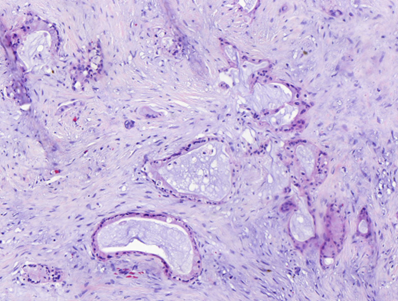

In particular, pancreatic cancer is characterized by highly desmoplastic tumors, in which the TME confers a dense and strong physical barrier preventing the access of anticancer treatments. Within, a spectrum of cell types co-exists, providing cancer cells with a notorious cancer cell plasticity and drug resistance capabilities. For instance, pancreatic cancer dense stroma is the result of cancer-associated fibroblasts (CAFs) activity, whose collagen secretion contributes to the formation of tight extracellular matrices (ECM) (Truong and Pauklin, 2021). CAFs and immune infiltrates have also been shown to modulate cancer cell phenotypes, supporting cancer cell adaptation, by paracrine signalling. In addition, coordinated action of Schwann cells and ECM remodelling capacities from CAFs have been proven to assist cancer cells during perineural invasion processes (Xue et al., 2023).

Figure 1. Neoplastic glandular structures surrounded by tumor microenvironment in a pancreatic ductal adenocarcinoma sample stained with Haematoxylin & Eosin.